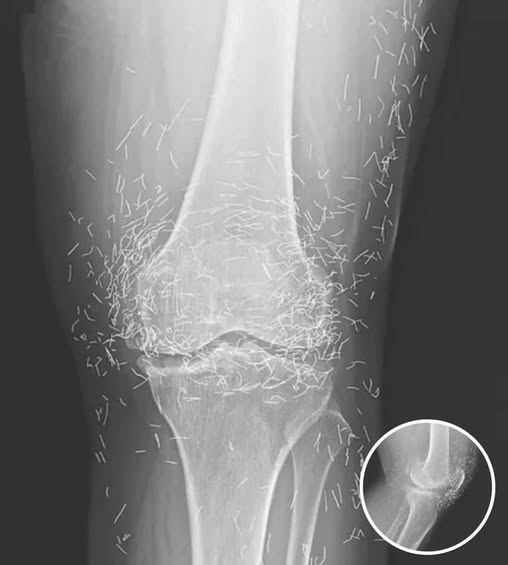

A X-ray of the patient’s knee showing acupuncture needles embedded in the tissue, Photo Credit: Reddit

As for the South Korean woman, her case was recently documented in the New England Journal of Medicine. While the needles may have been intended to help, her X-rays tell a cautionary tale about the potential risks of extreme alternative therapies.

A routine X-ray revealed an unexpected surprise when doctors examined the knees of a 65-year-old woman suffering from severe joint pain. What they found was nothing short of astonishing — hundreds of tiny gold needles embedded deep in her tissue.

There are other complications as well. Needles lodged in tissue can interfere with medical imaging. “They can obscure parts of the anatomy on an X-ray,” Guermazi noted. Even more alarming, patients with metal fragments in their bodies should never undergo an MRI, as the magnetic force could cause the needles to move — potentially puncturing blood vessels and causing life-threatening damage.